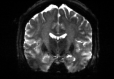

Refer to captionRefer to captionRefer to captioninitializationOptimal TransportRefer to captionRefer to captionRefer to captionOptimal Transport (blurred)Refer to captionRefer to captionRefer to captionMultilevelRefer to captionRefer to captionRefer to captionoptimizedRefer to captionRefer to captionRefer to captionRefer to captionRefer to captionRefer to caption

Figure 6: Example field maps (Subject ID 826353) at initialization (top row) and after optimization with Gauss-Newton (bottom row). The first column uses the proposed optimal transport initialization scheme. The middle column uses the same scheme with an additional Gaussian blur to promote smoothness. The right column uses the coarse-to-fine multilevel initialization scheme from HySCO with five levels, and the final field map is optimized at the original image resolution. The multilevel initialized field map is smooth by construction and further optimized to improve the relative image distance at the full resolution. The optimal transport initialization accurately corrects the distortions but is not smooth in the non-distortion dimensions unless blurred with a Gaussian. After the fine-level optimization all field maps are visually similar.